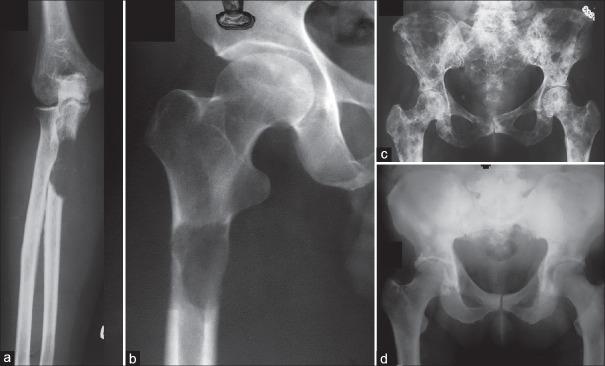

Skeletal metastasis is a common cause of severe morbidity, reduction in quality of life (QOL) and often early mortality. Its prevalence is rising due to a higher rate of diagnosis, better systemic treatment, longer lives with the disease and higher disease burden rate. As people with cancer live longer and with rising sensitivity of body imaging and surveillance, the incidence of pathological fracture, metastatic epidural cord compression is rising and constitutes a challenge for the orthopedic surgeon to maintain their QOL. Metastatic disease is no longer a death sentence condemning patients to "terminal care." In the era of multidisciplinary care and effective systemic targeted and nontargeted therapy, patient expectations of QOL, even during palliative end of care period is high. We lay emphasis on proving the diagnosis of metastasis by biopsy and histopathology and discuss imaging modalities to help estimate fracture risk and map disease extent. This article discusses at length the evidence and decision-making process of various modalities to treat skeletal metastasis. The modalities range from radiation including image-guided, stereotactic and whole body radiation, systemic targeted or hormonal therapy, spinal decompression with or without stabilization, extended curettage with stabilization, resection in select cases with megaprosthetic or biological reconstruction, percutaneous procedures using radio frequency ablation, cementoplasties and discusses the role of emerging modalities like high frequency ultrasound-guided ablation, cryotherapy and whole body radionuclide therapy. The focus lies on the role of multidisciplinary care, which considers complex decisions on patient centric prognosis, comorbidities, cost, feasibility and expectations in order to maximize outcomes on QOL issues.

骨转移是导致严重发病、生活质量(QOL)下降以及常出现早期死亡的常见原因。由于诊断率提高、全身治疗效果更好、患者带病生存时间延长以及疾病负担率上升,其患病率正在上升。随着癌症患者生存期延长以及身体成像和监测的敏感性提高,病理性骨折、转移性硬膜外脊髓压迫的发生率正在上升,这对骨科医生维持患者的生活质量构成了挑战。转移性疾病不再是宣判患者“临终关怀”的死刑判决。在多学科护理以及有效的全身靶向和非靶向治疗时代,即使在姑息性临终关怀阶段,患者对生活质量的期望也很高。我们强调通过活检和组织病理学来证实转移瘤的诊断,并讨论有助于评估骨折风险和描绘疾病范围的成像方式。本文详细讨论了治疗骨转移的各种方式的证据和决策过程。这些方式包括放疗,如影像引导放疗、立体定向放疗和全身放疗、全身靶向或激素治疗、有或无内固定的脊柱减压、扩大刮除术加内固定、在某些病例中进行假体或生物重建的切除术、使用射频消融、骨水泥成形术的经皮手术,并讨论了高频超声引导消融、冷冻疗法和全身放射性核素治疗等新兴方式的作用。重点在于多学科护理的作用,它考虑以患者为中心的预后、合并症、成本、可行性和期望等复杂决策,以最大限度地提高生活质量相关问题的治疗效果。